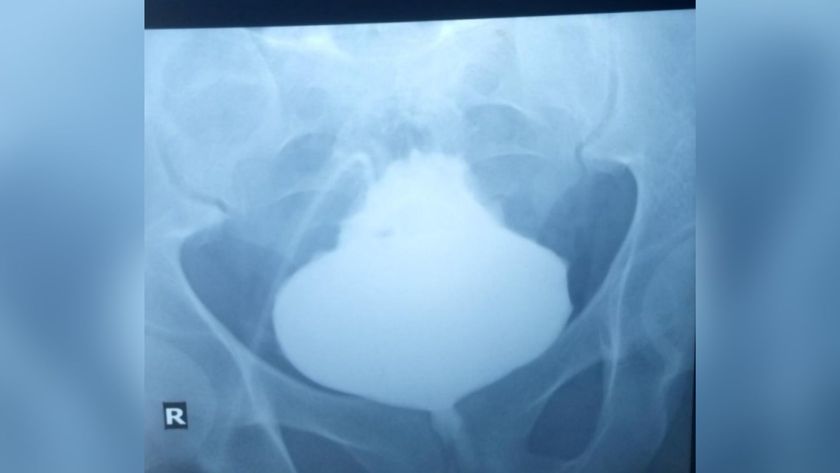

The 46-year-old man's symptoms were concerning but not particularly strange: He was losing weight, experiencing episodes of fainting and having trouble walking. But when doctors examined his eyes, they saw something odd: One of his pupils was smaller than the other, and it had an unusual, scalloped shape with irregular edges.

The strange shape of the man's pupil turned out to be due to a rare genetic condition, according to a new report of the case.

In patients with this type of FAP, the odd shape of the pupil results from two factors: amyloid deposits in the lens of the eye and abnormalities in the autonomic nervous system (the system that controls involuntary body functions), said Dr. Mark Fromer, an ophthalmologist at Lenox Hill Hospital in New York City, who was not involved with the man's case. Both of these problems result from the underlying genetic condition.

Fromer added that this condition is "extremely rare" and that the last time he saw a case like this was around 35 years ago, during his ophthalmology training.

Other eye problems that can result from FAP include severely dry eyes and secondary glaucoma, or glaucoma that results from an increase in eye pressure. There's no cure for eye problems tied to FAP, although doctors can treat symptoms such as dry eye and secondary glaucoma, Fromer told Live Science. The pupil abnormalities would not be treated, he said.